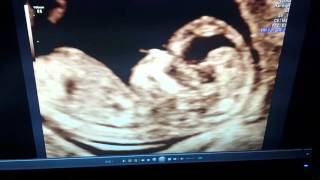

13 week ultrasound girl or boy ????

13 week ultrasound